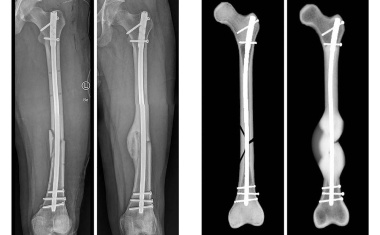

Komplikationen durch Infektionen sind nach dem Einsetzen von Implantaten keine Seltenheit. Das Risiko dafür steigt bei stark verschmutzten Wunden, die besonders in Kriegsgebieten wie der Ukraine häufig auftreten – aber gerade dort müssen viele Knochenverletzungen versorgt werden.